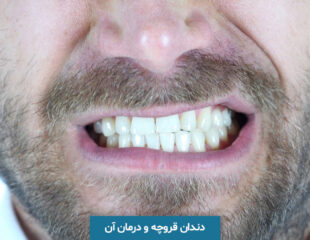

دندان قروچه چیست؟ مهم ترین روش های درمان دندان قروچه

به احتمال زیاد ممکن است برای شما هم اتفاق افتاده باشد که گاهی به دلایل مختلف از جمله عصبانیت و ...